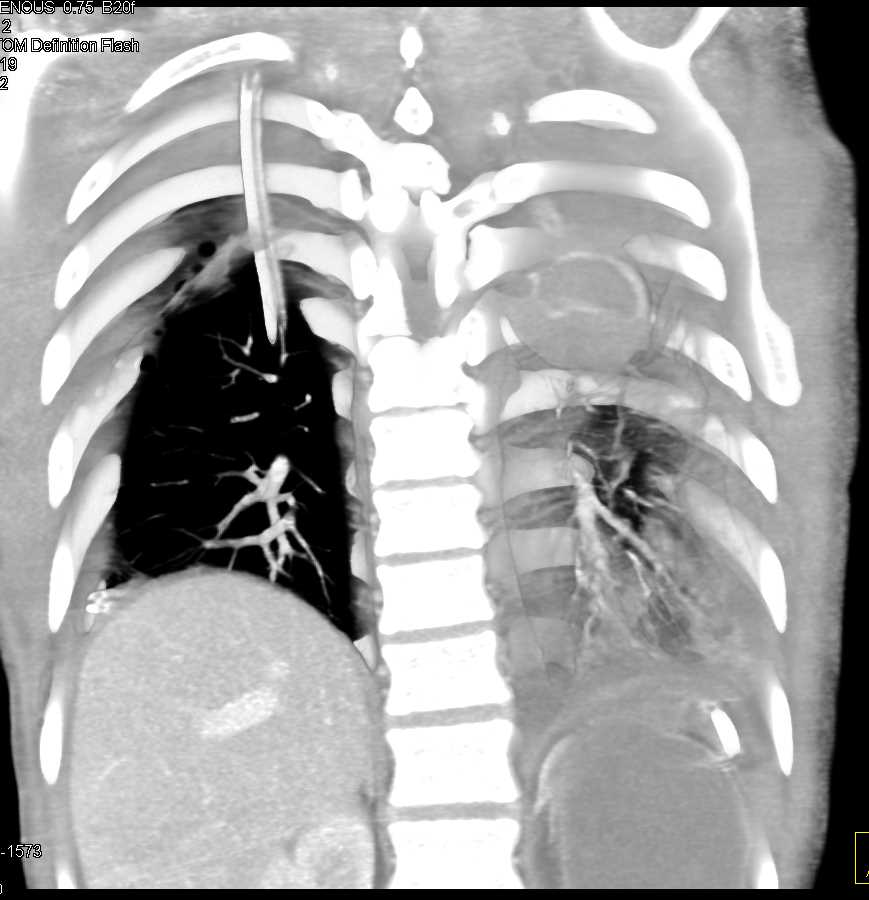

Pleural Based Hematoma